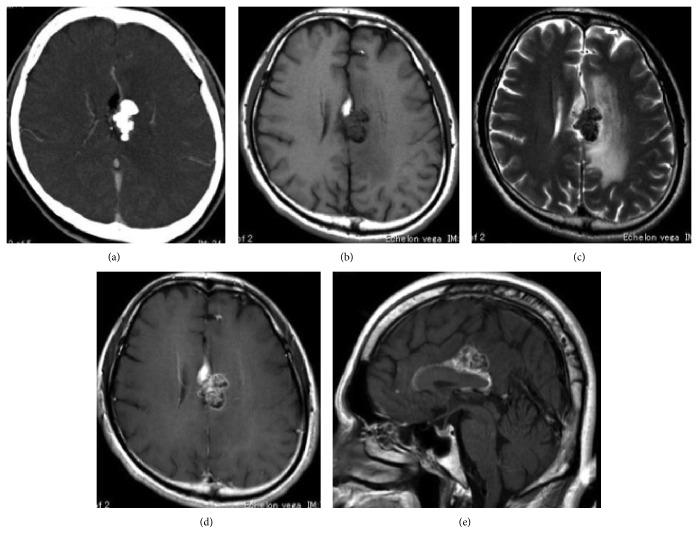

This report describes a rare case of a patient with lipoma presenting with epileptic seizures associated with expanding perifocal edema. The patient was a 48-year-old man who presented with loss of consciousness and convulsions. Magnetic resonance imaging (MRI) revealed a calcified mass in the corpus callosum with perifocal edema causing mass effect. An interhemispheric approach was used to biopsy the mass lesion. Histological examination revealed typical adipose cells, along with hamartomatous components. These components contained neurofilament and S-100-positive structures showing marked calcification. Fibrous cells immunoreactive for α-smooth muscle actin and epithelial membrane antigen proliferated with focal granulomatous inflammatory changes. MIB-1 index was approximately 5% in immature cells observed in granulomatous areas. We thus suspected a coexisting neoplastic component. The residual lesion persisted in a dormant state for 2 years following biopsy. Surgical resection of a lipoma is extremely difficult and potentially dangerous. However, in the present case, the lesion was accompanied by atypical, expanding, and perifocal edema. Surgical treatment was inevitable for the purpose of histological confirmation, considering differential diagnoses such as dermoid, epidermoid, and glioma. In the end, anticonvulsant therapy proved effective for controlling epileptic seizures.

本报告描述了一例罕见病例,一名脂肪瘤患者出现与病灶周围水肿扩大相关的癫痫发作。患者为一名48岁男性,表现为意识丧失和抽搐。磁共振成像(MRI)显示胼胝体有一个钙化肿块,伴有病灶周围水肿并产生占位效应。采用半球间入路对肿块病变进行活检。组织学检查显示典型的脂肪细胞以及错构瘤成分。这些成分包含神经丝和S-100阳性结构,显示明显钙化。对α平滑肌肌动蛋白和上皮膜抗原呈免疫反应的纤维细胞增殖,并伴有局灶性肉芽肿性炎症改变。在肉芽肿区域观察到的未成熟细胞中,MIB-1指数约为5%。因此,我们怀疑存在并存的肿瘤成分。活检后,残留病变处于休眠状态持续了2年。脂肪瘤的手术切除极其困难且具有潜在危险性。然而,在本病例中,病变伴有非典型、扩大的病灶周围水肿。考虑到诸如皮样囊肿、表皮样囊肿和胶质瘤等鉴别诊断,为了进行组织学确诊,手术治疗是不可避免的。最后,抗惊厥治疗被证明对控制癫痫发作有效。